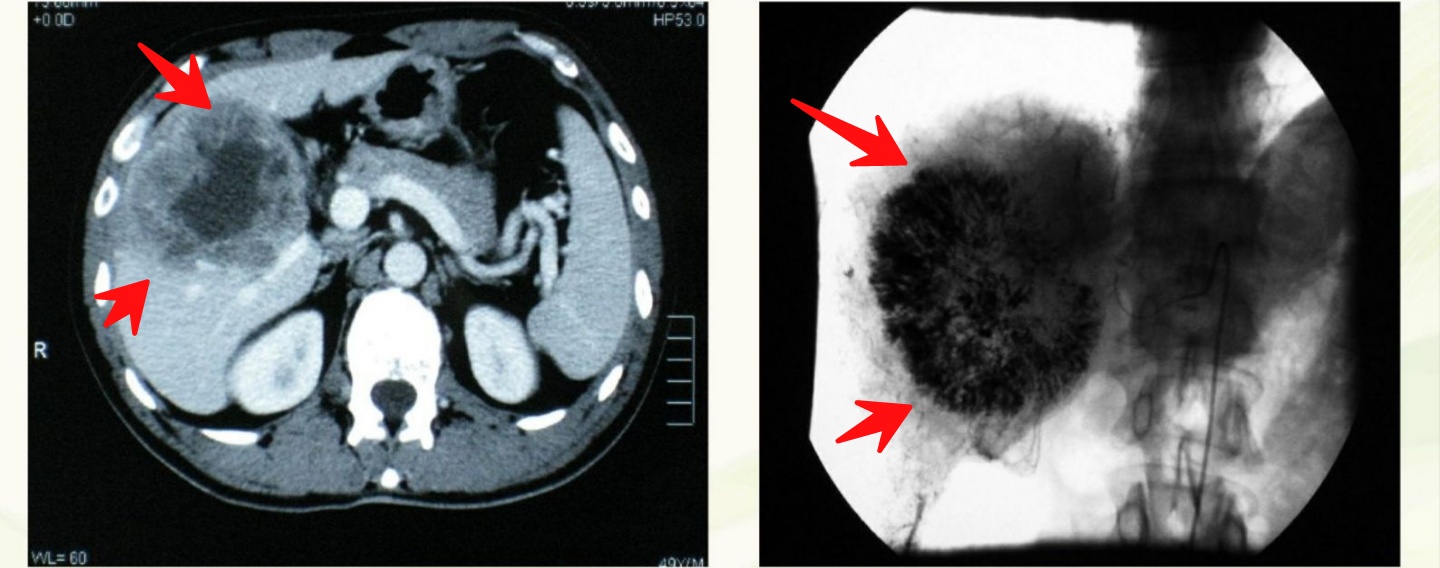

病例:男性,48岁,乏力,间断性右上腹痛1年

肝右叶肿块,中心有坏死,符合肝癌,已经8cm了,综合考虑后选择了介入治疗。

先后做了3次TACE(经导管肝动脉化疗栓塞),显示肿瘤明显缩小:

复查增强CT,发现有部分存活的肿瘤组织,又联合了射频消融治疗,再次复查肿瘤继续缩小,肝右叶萎缩,肝左叶代偿性肥大,AFP(甲胎蛋白,原发性肝癌的重要肿瘤标志物)也恢复正常:

该患者已经生存了接近5年。